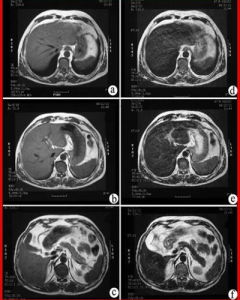

增強掃描就是把藥從靜脈(一般為肘前靜脈)注入血管內同時進行CT掃描,可以發現平掃(沒有向血管內注藥掃描)未發現的病灶,主要用於鑑別病變為血管性或非血管性,明確縱膈病變與心臟大血管的關係,了解病變的血供情況以幫助鑑別良、惡性病變等。增加病灶的信息量,以便於對病灶定性分析甚至明確診斷.

CT檢查是眾多醫學影像診斷技術中的一種,其診斷疾病的一個特點就是測量X射線通過人體後的衰減值,反應X射線衰減值的專業術語為密度,CT診斷學上用“CT值”來描述密度的差異。相同的組織結構應是相同的密度,也就是說正常的組織器官如肝臟的密度是比較均勻的。但是某些病變如腫瘤,其生長在正常的組織器官中,早期因數目少、體積小,當採用普通CT掃描時,腫瘤組織與周圍的正常組織可以表現為相同或相似的密度,這樣CT醫生往往因無法發現病變而報告正常。但若此時再行增強掃描(指靜脈注射造影劑後的掃描),病變部位可發現異常的強化現象,從而與正常的組織區分開來,這樣就可以早期發現病變,及早進行科學、合理的治療,既可以治癒疾病,又可降低治療費用。因此,增強掃描絕非“多此一舉”,應積極配合醫生的檢查,以免留下不可挽回的遺憾。